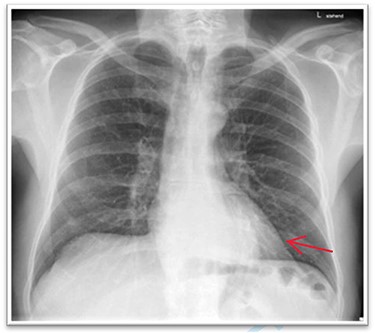

A 63-year-old male patient underwent a medical check-up due to acute bronchitis. The patient’s body mass index was 24.7 kg/m2, he was in good physical condition and no further pathological findings were revealed during clinical examination. Chest X-ray showed a retrocardiac mass (Fig. 1) and a subsequent CT scan indicated a lipomatous mass in the lower posterior mediastinum measuring 10 × 4.4 × 10.6 cm. A vascular pedicle reaching into the abdominal cavity suggested paraesophageal herniation of a large portion of the greater omentum (Fig. 2). The patient was referred to the surgical department suffering from a retrosternal feeling of pressure aggravated in supine position, with a differential diagnosis of lipomatous tumour. No symptoms of gastroesophageal reflux disease were reported, and the clinical examination showed no abnormalities. Preoperative work-up included a gastroscopy and contrast medium swallow. Endoscopy showed an axial hernia of 4 cm without further irregularities or signs of a reflux disease. Passage appeared physiological with no signs of gastroesophageal reflux and orthotopic positioning of the oesophagogastric junction.

The barium oesophagogram showing a near to total stenosis caused by alimentary bolus.